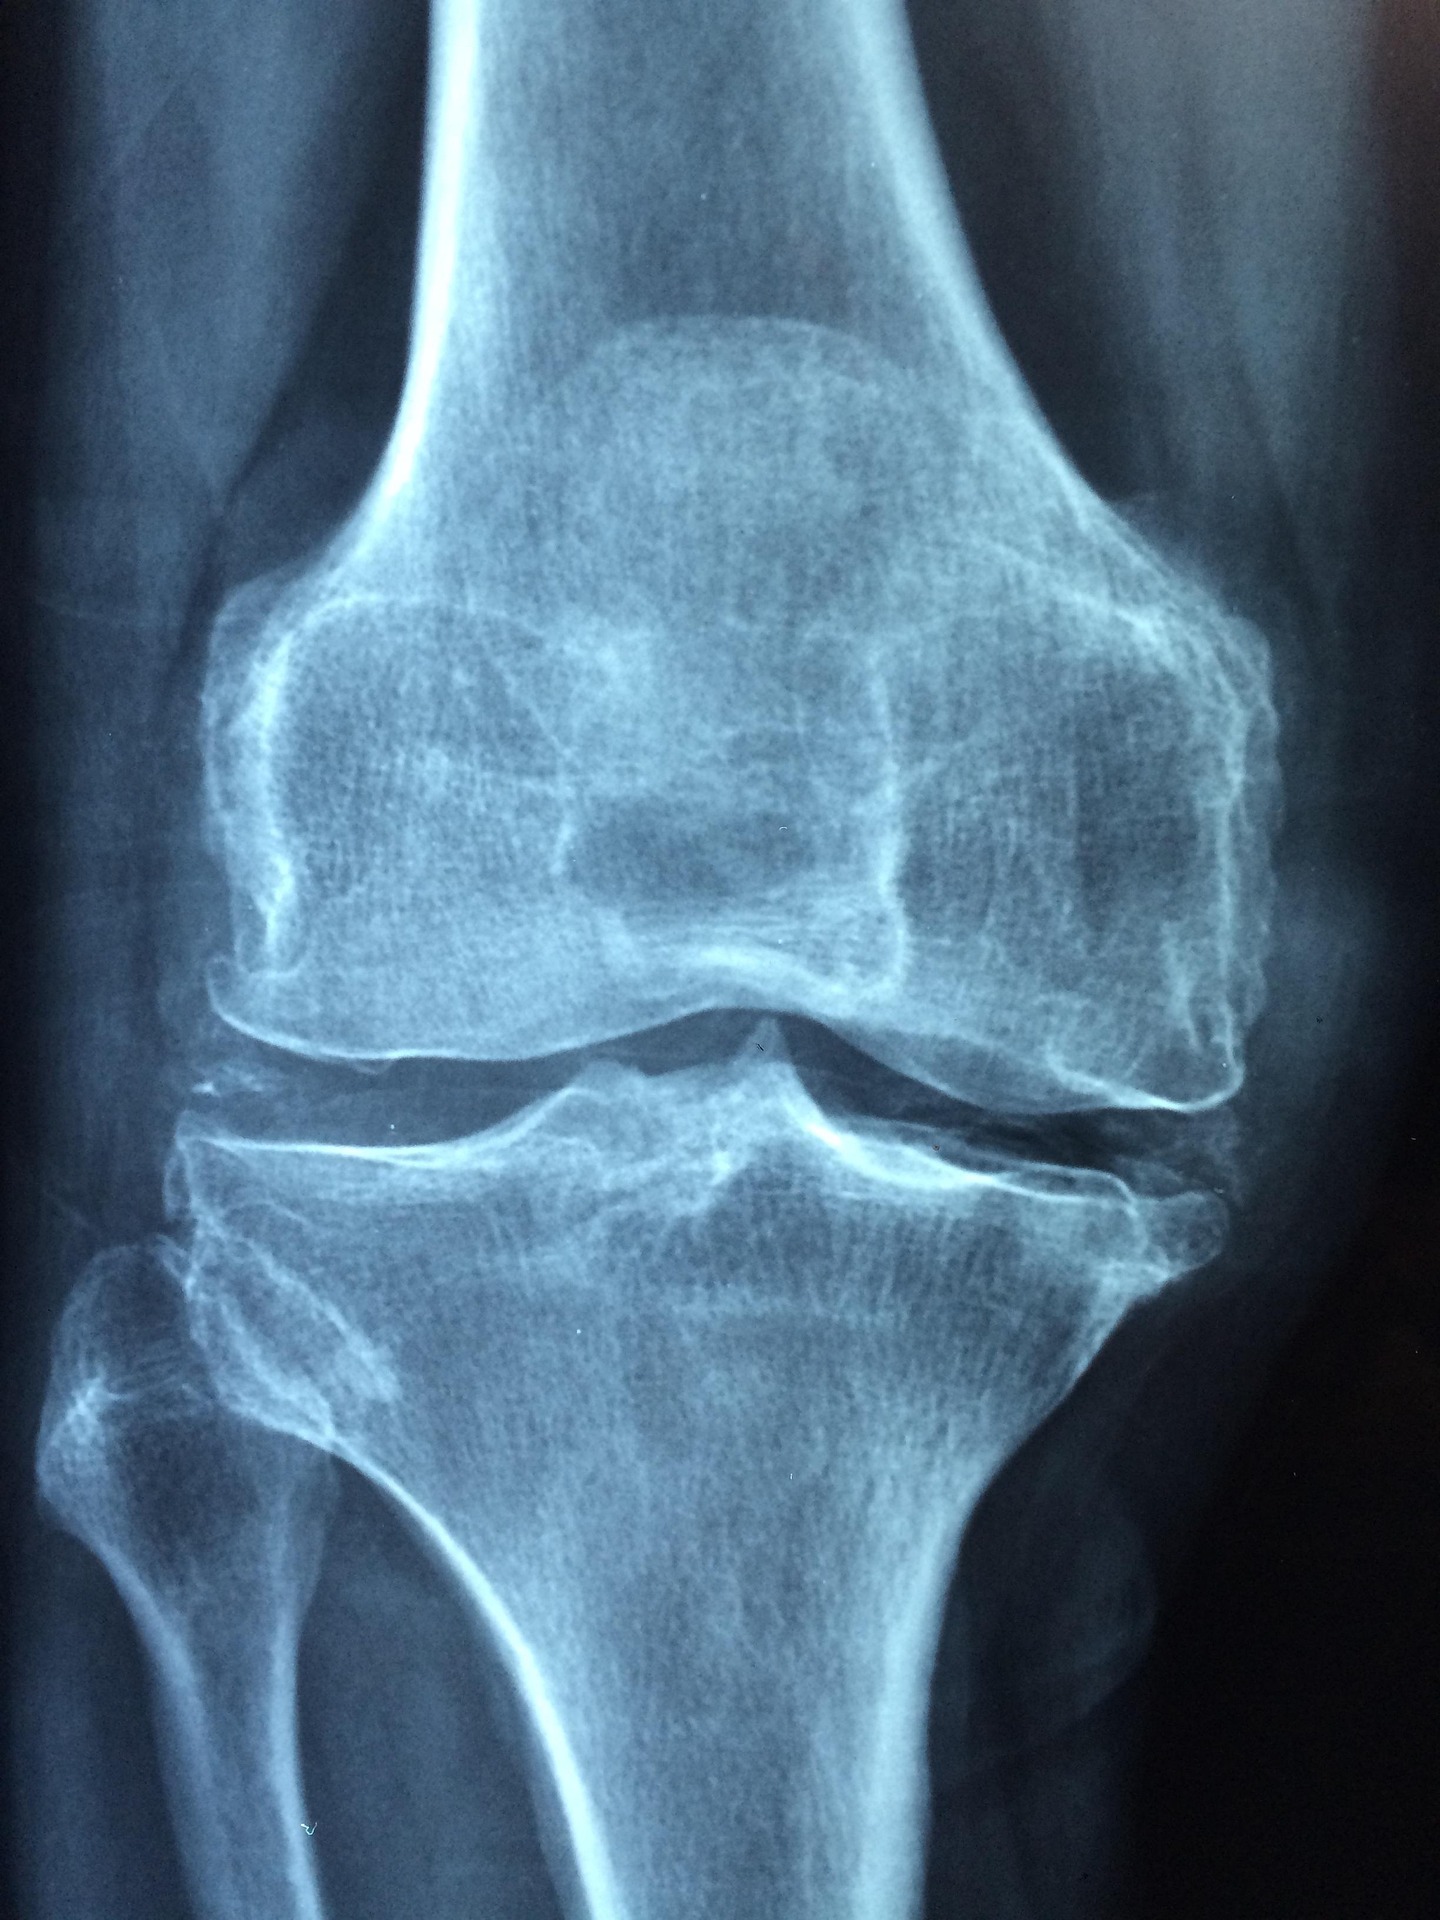

Las lesiones del menisco son una de las afecciones más comunes en deportistas, y su tratamiento quirúrgico, aunque altamente eficaz, necesita de una adecuada readaptación deportiva para evitar recaídas y maximizar el rendimiento.

Estudios científicos recientes, como los de Smith et al. (2021), Martinez et al. (2020) y Lopez et al. (2019), han demostrado que la implementación de protocolos de rehabilitación temprana y específica mejora significativamente la funcionalidad de la rodilla y acelera el retorno a la actividad deportiva.

La importancia de esta recuperación no solo se basa en la restauración de la movilidad, sino también en la prevención de complicaciones y en la optimización del rendimiento físico postoperatorio.